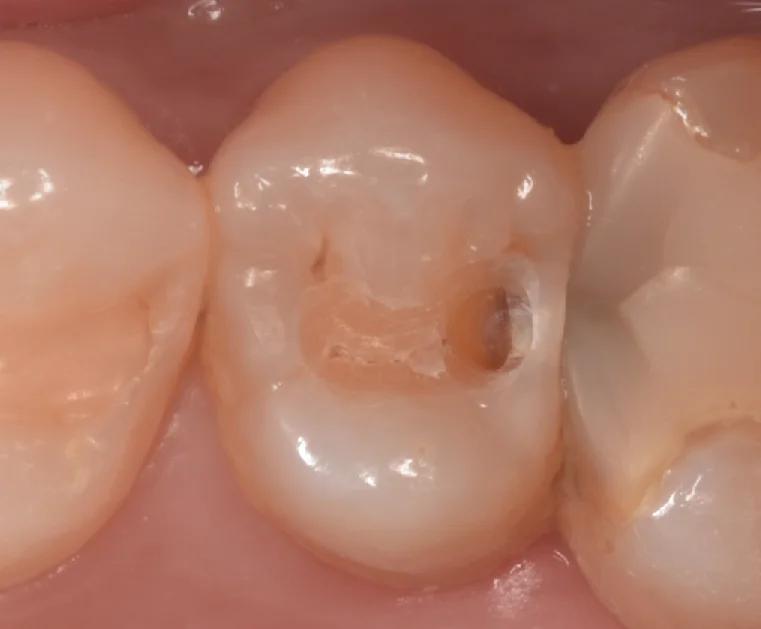

古い詰め物だけ除去して虫歯が見えやすい状態にしたのがこちらになります。

歯との間側がやや茶色く変色しているのがわかりますかね?

術前診査だと、そこまで内部で大きくなっていないだろうなという予測だったのですが・・・

取り切ってみると・・・。

こんな感じで結構なサイズでした。